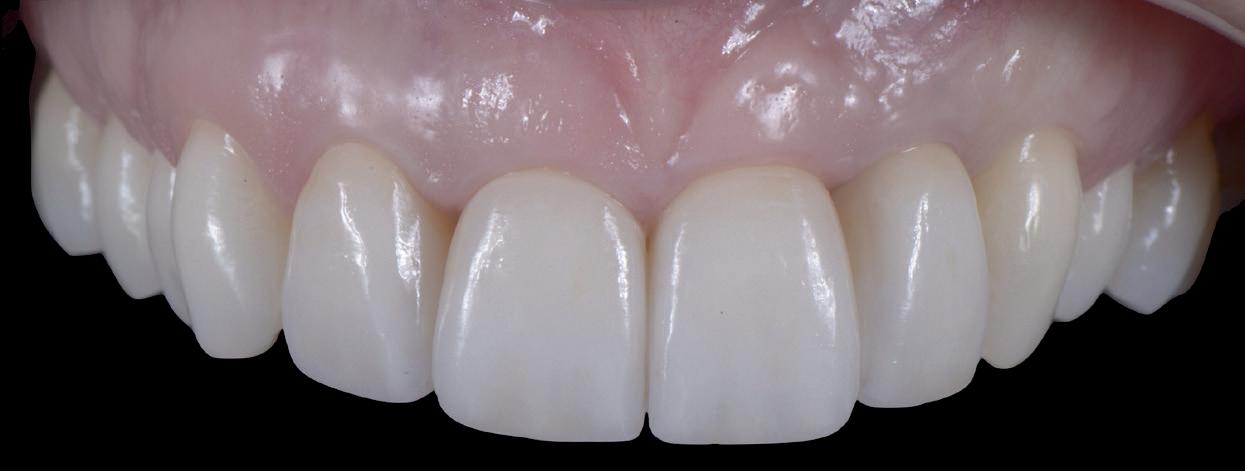

De flap en graft worden met poly-propelene 6.0 hechtingen gefixeerd. De tijdelijke reconstructie wordt herplaatst (foto 17-20).

Na 4-6 weken kan het aangebrachte healing abutment worden vervangen door een tijdelijk abutment. Deze wordt aan de kunststof reconstructie verbonden om zo de gingiva ter plaatse van de 22 te vormen. Zo lijkt het of er geen implantaat maar nog steeds een wortel aanwezig is, wat het esthetisch eindresultaat ten goede zal komen (foto 21-23). Vanaf 4-6 maanden ziet het weefsel er gezond uit. Nu kan met de uiteindelijke restauratiefase worden gestart (foto 24 en 25).

Er wordt een afdruk of een intra-orale scan genomen van de situatie met tijdelijke voorzieningen en de geprepareerde situatie. Ook mag een portretfoto en mondfoto niet ontbreken. Al deze informatie gaat naar het laboratorium zodat de onderstucturen van de restauraties gemaakt kunnen worden (foto 26).

De vier restauraties worden in samenspraak met de ceramist en de patiënt gecustomized. Op dit moment kunnen er nog details worden aangepast om zo het mooiste eindresultaat te behalen.

Bij de evaluatie van deze casus blijkt dat het herstellen van de processen alveolaris ter plaatse van de 22 is gerealiseerd en dat de gingiva qua positie en volume rond de 22 en 23 is verbeterd. Het implantaat is goed ge-osseointegreerd en de gingiva rond het implantaat heeft een natuurlijke vormgeving gekregen. De kronen zijn met moderne technologie en esthetisch hoogwaardig vervaardigd door het Oral Design Center Holland. Met dank aan Eric van der Winden.

De dentale mediaanlijn is rechtop gezet, maar staat niet helemaal gelijk met de faciale mediaan. Echter, mevrouw is functioneel en esthetisch naar tevredenheid afbehandeld (foto 27-30).